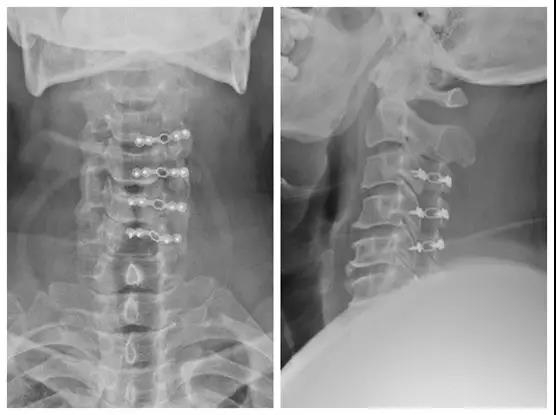

颈椎后路单开门椎管扩大成型手术(微型钛板固定)

患者:郑某,男,48岁 ;

主诉:双上肢麻木1年,加重伴行走不稳半年;

查体:双前臂外侧、手掌皮肤感觉减退。三角肌左/右=IV/V,肱二头肌左/右=IV/V,肱三头肌左/右=IV/V,指深浅屈肌左/右=IV/V,小指展肌左/右=IV/V。左肱三头肌反射、肱二头肌反射、桡骨膜反射活跃。双侧Hoffmann征阳性。

诊断:颈椎管狭窄症

术前X线正侧位片

术后X线正侧位